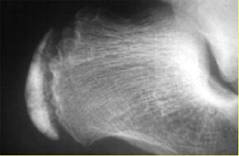

Le bilan radiologique ne doit pas servir à établir un diagnostic, mais à mettre en évidence un éventuel diagnostic différentiel : « fracture de fatigue, ostéite ou talonnade ».

La radiographie ne montre pas toujours la classique densification du noyau apophysaire ou irrégularité de la bande métaphysaire.